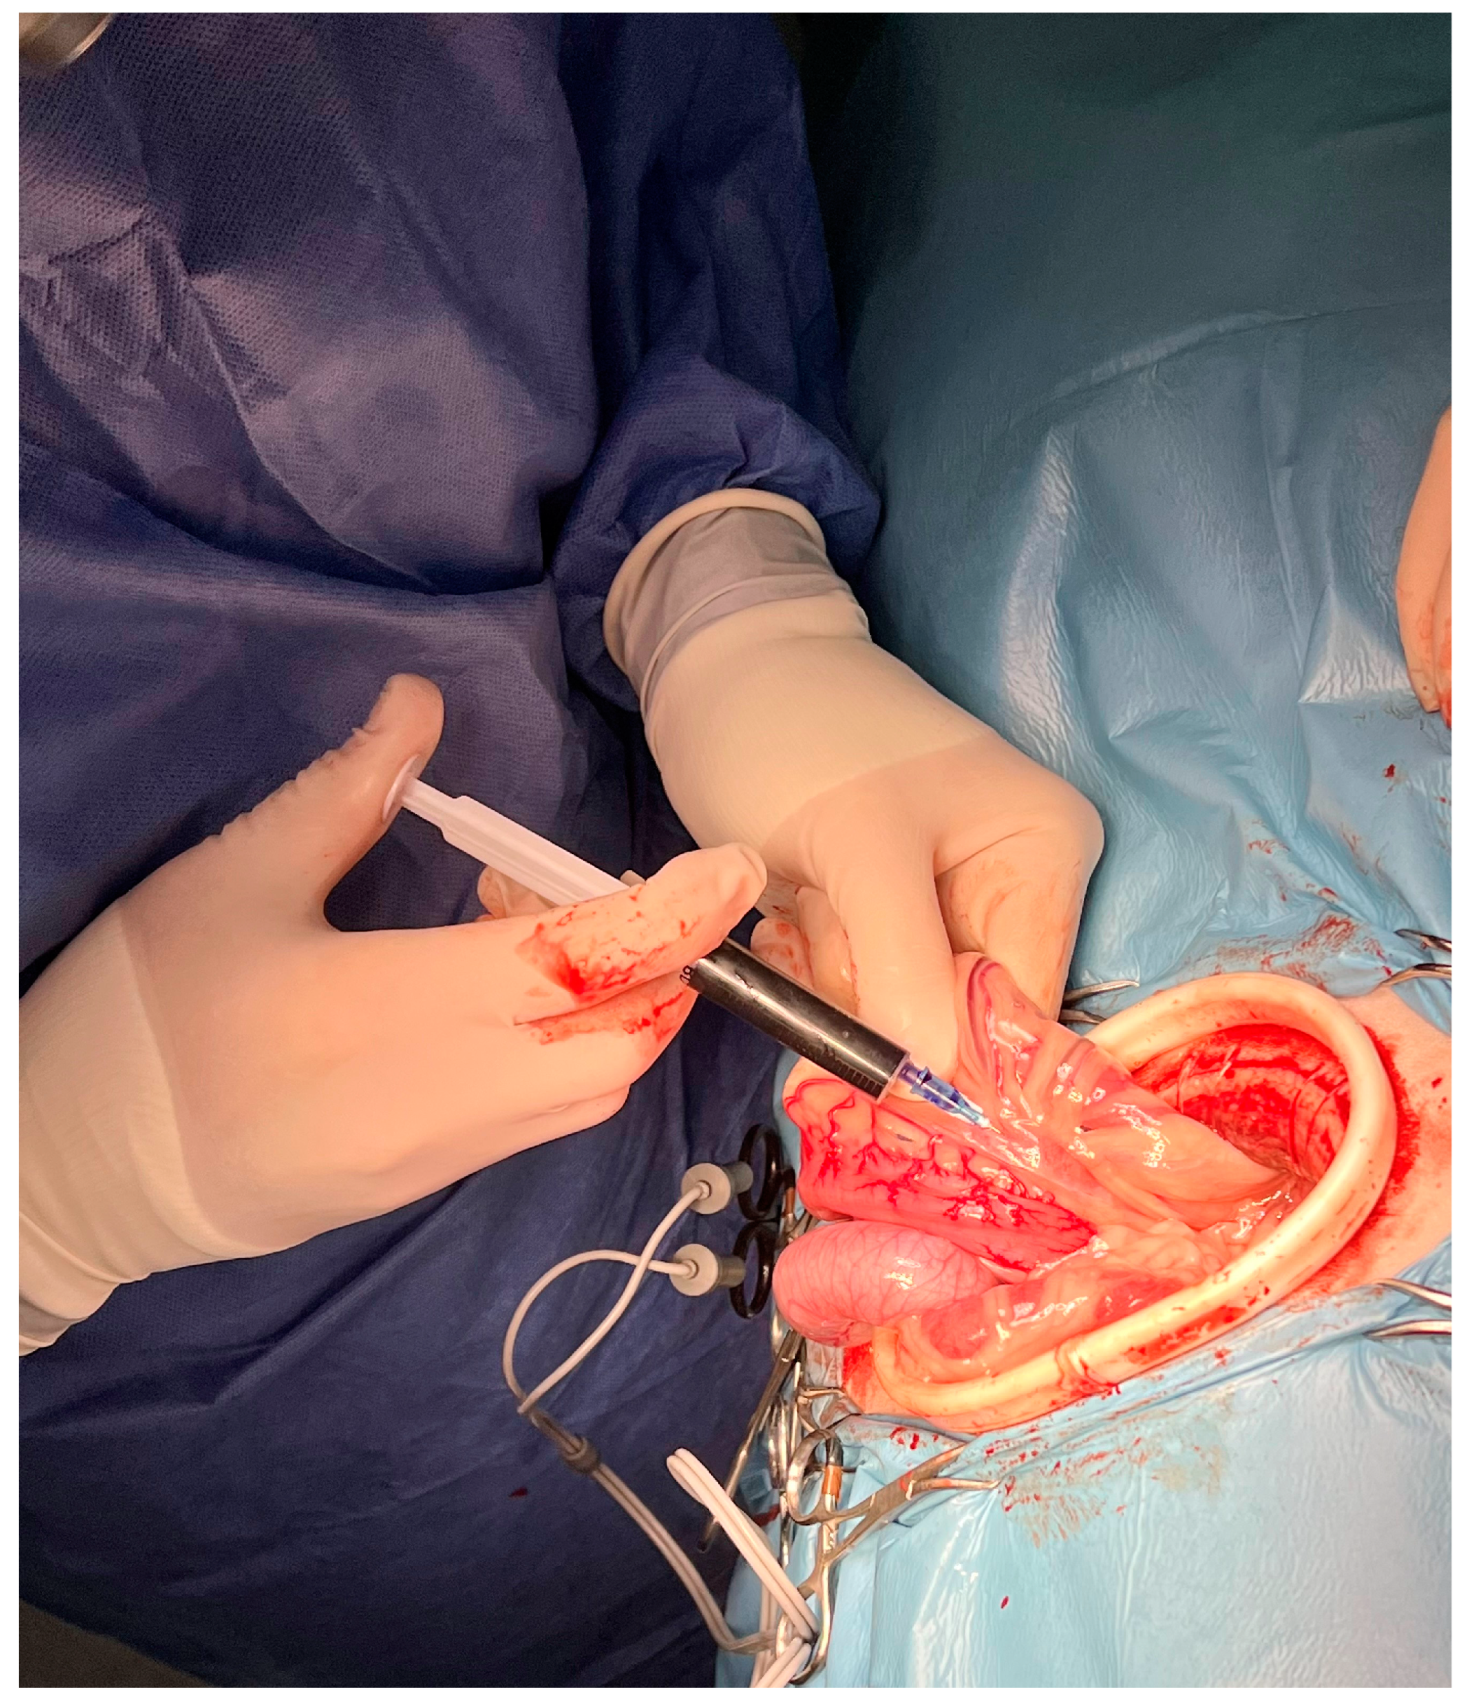

2. Materials and Methods

2.2. Surgery